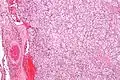

On microscopic inspection, the tumor cells are readily recognized. Individual tumor cells are polygonal to oval and are arranged in distinctive cell balls, called Zellballen.[8] These cell balls are separated by fibrovascular stroma and surrounded by sustentacular cells.

By light microscopy, the differential diagnosis includes related neuroendocrine tumors, such as carcinoid tumor, neuroendocrine carcinoma, and medullary carcinoma of the thyroid.

With immunohistochemistry, the chief cells located in the cell balls are positive for chromogranin, synaptophysin, neuron specific enolase, serotonin, neurofilament and Neural cell adhesion molecule; they are S-100 protein negative. The sustentacular cells are S-100 positive and focally positive for glial fibrillary acidic protein. By histochemistry, the paraganglioma cells are argyrophilic, periodic acid Schiff negative, mucicarmine negative, and argentaffin negative.

Micrograph of a carotid body tumor